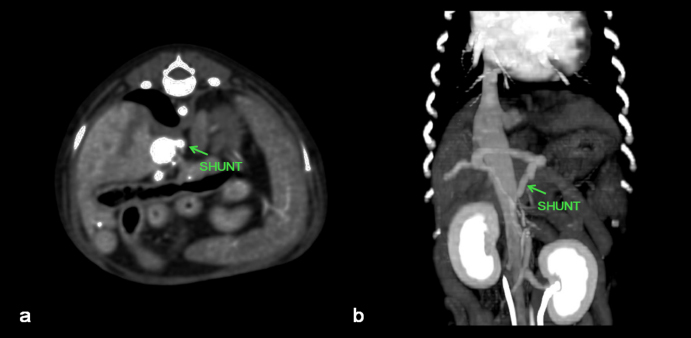

A 1-year-old neutered male Maltese dog weighing 1.4 kg was referred to the Veterinary Teaching Hospital showing microhepatica (Fig. 1a) and hyperammonemia. The dog did not show clinical signs related to portosystemic shunt previously. Although its postprandial ammonia level was in the reference range [18 μmol/l, reference interval (RI): 0–98 μmol/l], hypoalbuminemia (2.1 g/dl, RI: 2.6–3.3 g/dl) and increased levels of serum bile acid (177 μmol/l, RI: 0–25 μmol/l), alanine transaminase (ALT) (254 IU/l, RI: 21–102 IU/l), and alkaline phosphatase (ALP) (1347 IU/l, RI: 29–97 IU/l) were identified. No abnormalities, including cardiac murmur, were observed during physical examination. For a more thorough examination, computed tomography was used, and a CPSS (porto-caval shunt) was diagnosed (Fig. 2a and b). After preoperative medical stabilization, surgery was performed for shunt attenuation. Anesthesia was induced with propofol (8 mg/kg, IV) and maintained by isoflurane. Perioperative pain was managed by tramadol (5 mg/kg, IV). From the xiphoid process to the pubis, a standard ventral midline approach was taken. After dissecting the shunt from surrounding tissues, portal pressure was measured from the jejunal vein. Baseline portal pressure was measured to be approximately 7–8 mmHg (RI: 6–10 mmHg). It increased to 13–14 mmHg after temporary complete occlusion of the shunt. The shunt was attenuated using a cellophane band. The abdominal cavity was closed in a routine manner. Its recovery from anesthesia was uneventful. Postprandial serum bile acid (12 μmol/l), albumin (2.6 g/dl), and ALT (29 IU/l) levels returned to their normal ranges at 1 month after the operation. Its serum ALP level also decreased to 430 IU/l, although it was above the RI. An increase in liver size was observed by abdominal radiographs 1 month after surgery (Fig. 1b). Because the majority of the CPSS anomalies were cured throughout the follow-up period, the dog was able to return to normal life without the need for supporting medicine. One year after surgery, the dog was presented to the Veterinary Teaching Hospital for exercise intolerance. Blood gas analysis revealed hypoxemia (73.6%, RI: 95%–99%). A cardiac murmur was auscultated. When compared with thoracic radiographs evaluated at the time of the operation (Fig. 3a and b), the vertebral heart scale increased from 10 to 11.7, indicating generalized cardiomegaly (Fig. 3c and d). Following echocardiography revealed ASD and pulmonary hypertension (Fig. 4a and b). A bubble study confirmed right-to-left shunt. Surgical or interventional therapy was not contemplated due to the dog's tiny size (1.7 kg) and reversed interatrial shunt. Thus, medical treatment was performed to reduce pulmonary hypertension (sildenafil, 1.5 mg/kg, PO, q12 hours). Hypoxemia was improved (94%) after a month of treatment. The dog's activity intolerance had been overcome, according to the owner. As a response to the medical treatment was generally good, therapy was still maintained without changing medication for the next 16 months after diagnosis of the ASD.

Fig. 2. Cross (a) and sagittal (b) views of CT images showing a congenital extrahepatic portosystemic shunt.